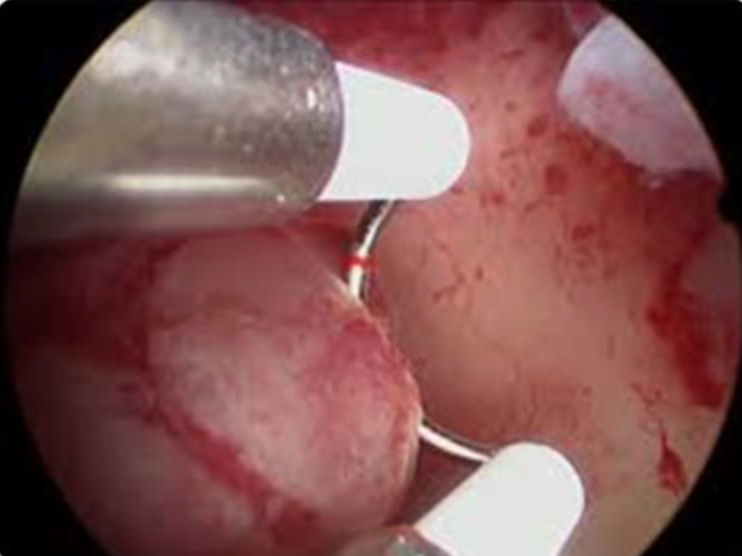

A histeroscopia cirúrgica é considerada o método de escolha para o tratamento do pólipo endometrial.

Suas principais vantagens são:

O princípio técnico é simples:

A ressecção deve ser sempre direcionada da região fúndica em direção ao colo uterino, evitando movimentos bruscos ou caudo-craniais que possam levar à perfuração.

A polipectomia geralmente é realizada em centro cirúrgico com sedação/anestesia geral, especialmente para aqueles pólipos que apresentam base séssil ou é muito volumoso.